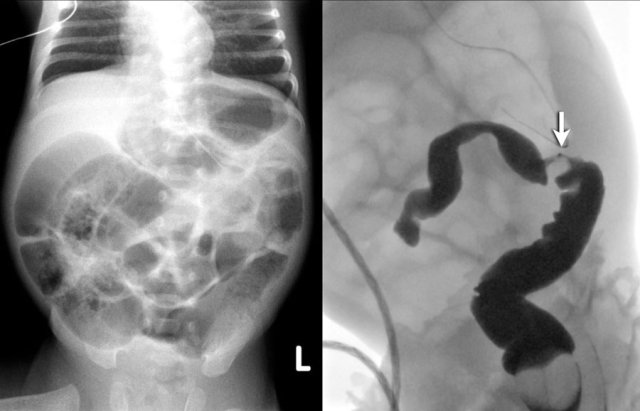

The image on the left is taken 6 days after birth and shows distended bowel with pneumatosis intestinalis.

A colon enema at 6 weeks of age shows a stricture in the colon descendens (arrow).

Here a long stricture in the colon transversum in a child who had a NEC.